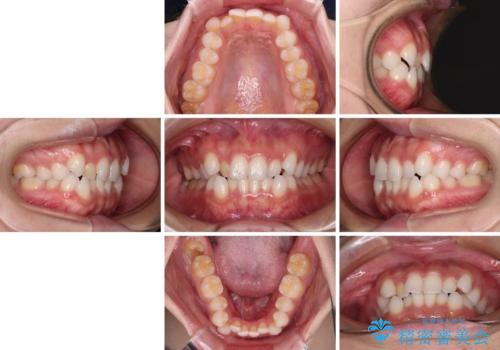

- 前歯のデコボコとクロスバイトを気にして来院された患者様です。

上下ともにデコボコはそれほど強くありませんでしたが、非抜歯では口元が突出した仕上がりとなる可能性があるため、上下左右の第一小臼歯4本を抜歯し、ワイヤー装置での抜歯矯正を行うこととしました

スペースを閉じるために期間を要しましたが、無事に綺麗な口元に仕上げることができました。